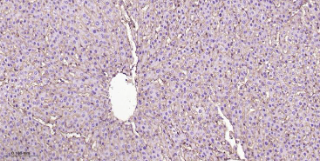

Immunohistochemical analysis of paraffin embedded Rat liver tissue slide using IHC0521R (Rat Integrin beta 1 Kit).